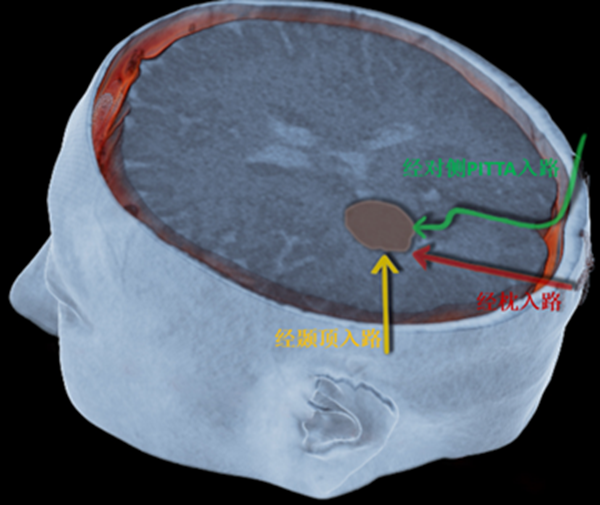

仔細查看患者影像資料后,謝主任決定另辟蹊徑:放棄既往到達腫瘤路徑較短但創(chuàng)傷較大的“直線”通路,選擇更為微創(chuàng)但手術(shù)路徑較長的“彎道”。

“之所以選擇繞彎子,是為了避開視覺通路等重要神經(jīng)功能區(qū),抵達深部腫瘤部位,最大程度地保護神經(jīng)功能區(qū)?!敝x主任的講解,讓崔阿姨打消了顧慮,決定接受手術(shù)。

仔細的術(shù)前檢查及評估后,神經(jīng)外科全內(nèi)鏡手術(shù)團隊開展了病例討論,大家一致認同后枕部直切口,全神經(jīng)內(nèi)鏡下經(jīng)對側(cè)后縱裂-大腦鐮-楔前葉入路切除左側(cè)腦室三角區(qū)腦膜瘤這一手術(shù)策略。謝主任解釋,該手術(shù)方案的特點在于:1、充分利用了重力導(dǎo)致腦組織的自然塌陷;2、充分利用了后縱裂的自然腔隙;3、充分利用了楔前葉這一功能啞區(qū);4、充分利用了對側(cè)入路,使得手術(shù)操作角度更為直接?;谶@4個特點,讓這一深部手術(shù)從切口到腫瘤切除均能實現(xiàn)最大化的微創(chuàng)。

相較于傳統(tǒng)的手術(shù)路徑,經(jīng)對側(cè)后縱裂-大腦鐮-楔前葉入路(PITTA)的優(yōu)勢非常明顯:該入路能最大程度避開視輻射及視覺皮層中樞,最大程度保護視覺通路,大大降低了術(shù)后視覺障礙的發(fā)生;在手術(shù)過程中,可在早期直視下控制脈絡(luò)叢的腫瘤的供血動脈,避免了盲目的電凝燒灼,不僅能提高腫瘤的全切率,還能降低術(shù)后相關(guān)并發(fā)癥的出現(xiàn)。

不過,該入路手術(shù)路徑長,通道狹窄,既往顯微鏡手術(shù)很難提供清晰的視野照明,而神經(jīng)內(nèi)鏡能發(fā)揮抵近觀察的特點,為順利切除腫瘤,提供良好的深部視野照明。手術(shù)需要首先從對側(cè)縱裂進入兩側(cè)頂葉半球之間,切開大腦鐮,然后找到楔前葉,經(jīng)楔前葉進入側(cè)腦室三角部,才能順利達到腫瘤所在部位,因此術(shù)者不僅要有嫻熟的全內(nèi)鏡操作技術(shù),還要有過硬的心理素質(zhì)和扎實的腦神經(jīng)解剖學知識。